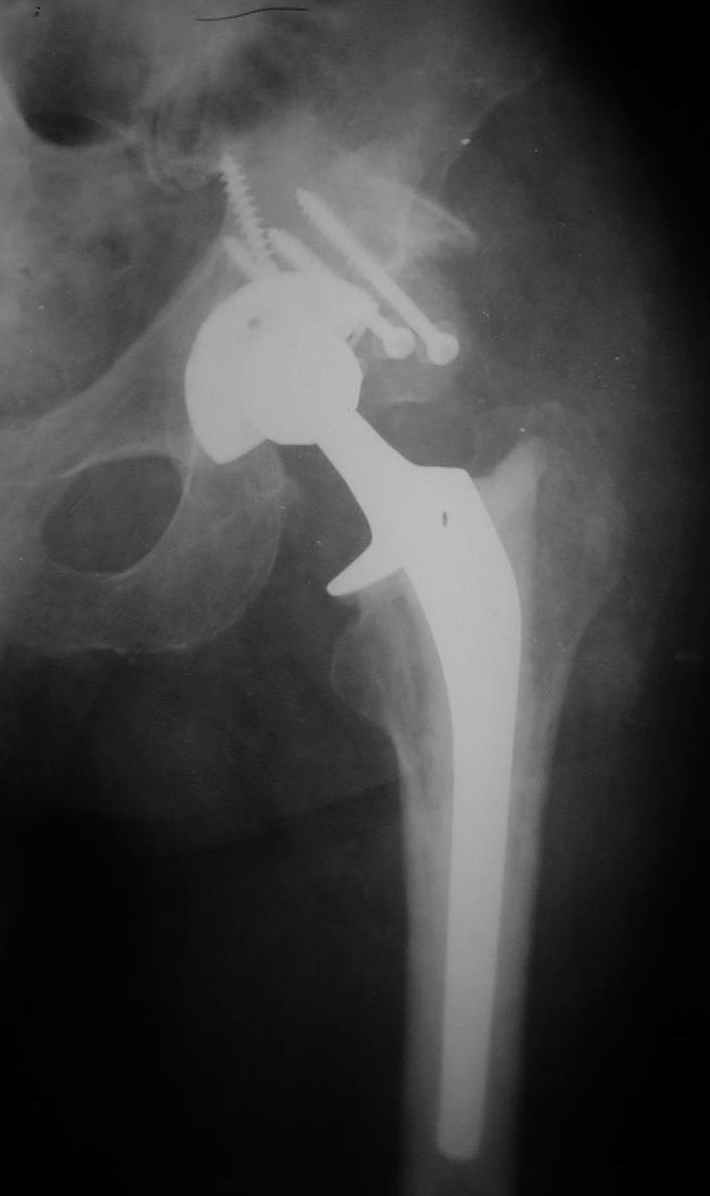

В институте совместно с фирмой Зиммер достаточно регулярно (практически ежемесячно) проводятся 2-х недельные циклы по различным вопросам эндопротезирования. Если есть возможность и желание, мы готовы поделиться с Вами нашим опытом, тем более есть что показать и что обсудить - в настоящее время ежедневно выполняется от 6 до 10 эндопротезирований коленного и тазобедренного сустава. В качестве примеров хочу показать 2 наблюдения, через 1 год и 5 лет после операции

5 лет